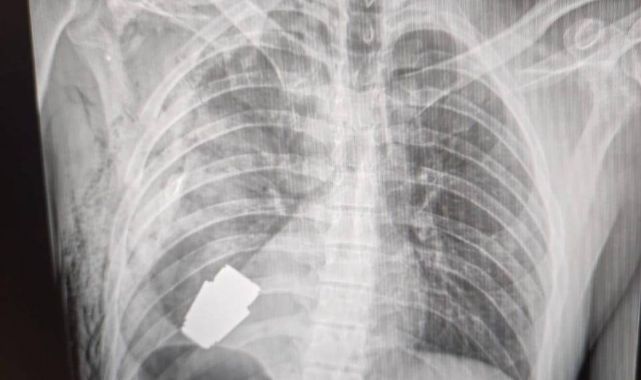

Ukrayna'da bir askerin kalbine yakın bölgesinde patlamamış VOG el bombası tespit edildi. Bombanın her an patlayabilme ihtimali olduğu için Ukrayna Silahlı Kuvvetlerinin en deneyimli cerrahlarından biri olan Andrii Verba tarafından acil bir operasyon gerçekleştirildi. Ukrayna Savunma Bakanı Yardımcısı Hanna Maliar, cerrahi müdahalenin başarılı olduğunu ve askerin tedavi altına alındığını söyledi. El bombasının askerin vücuduna nasıl girdiğine dair ise açıklama yapılmadı.

Ukrayna'da bir askerin kalbine yakın bölgesinde VOG el bombası tespit edilmesinin ardından gerçekleştirilen ameliyat sonucu patlayıcı başarılı bir şekilde çıkarıldı.